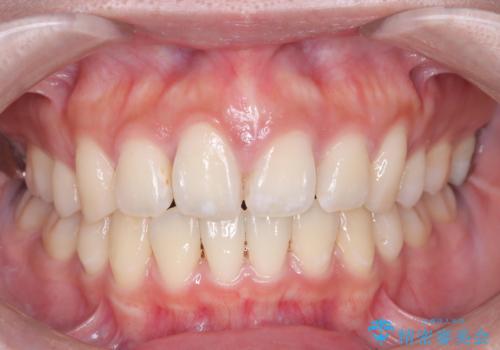

口元の突出感を解消し、横顔を美しく整えるワイヤー矯正

今回の矯正治療では、口元の突出感を解消するためのスペースを確保するため、計画通り上下左右4本の小臼歯を抜歯しました。装置には、確実な歯の移動と細やかな調整が可能なワイヤー矯正を採用。抜歯によってできたスペースを最大限に利用し、前歯を奥へ、そして垂直的に慎重に移動させました。

治療の結果、長年のコンプレックスであった口元の突出感が大幅に解消され、横顔のライン(Eライン)が美しく改善しました。機能的な咬み合わせを確立すると同時に、患者様が望んでいた審美的な口元を獲得していただけました。